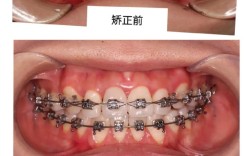

- 面部突度与侧貌:对于“龅牙”(双颌前突)患者,拔牙可内收前牙,改善唇部与面部的协调性。

- 双颌前突(龅牙),需内收前牙改善侧貌;

A:不会,正畸拔牙通常选择前磨牙(位于牙弓中段),拔除后牙齿向内移动,主要改善的是“凸嘴”问题,使面部轮廓更柔和,而脸型饱满度主要由颧骨、下颌骨等骨骼支撑,以及软组织(肌肉、脂肪)决定,拔牙不会影响骨骼结构,也不会导致“脸塌”,部分患者因牙齿内收后,嘴唇支撑减少,可能出现轻微“显老”感,但这是暂时的,随着软组织适应和稳定,面部会恢复自然美观。